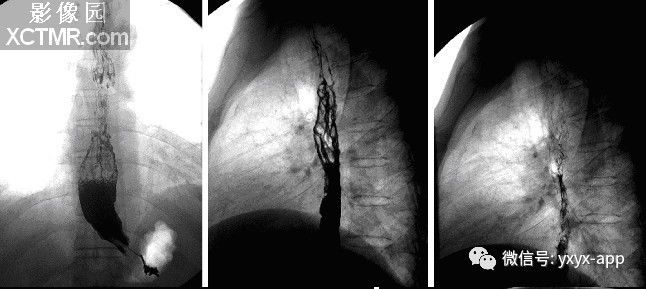

【影像表现】X线吞钡:食管下段迂曲,管壁呈锯齿状改变,粘膜皱襞增宽、增粗,扭曲呈蚯蚓状,并可见串珠状充盈缺损,食管稍扩张,管壁轮廓凹凸不平,钡剂排空延迟。管壁柔软,舒缩功能良好。 CT平扫及增强扫描可见食管内多发类圆形稍低密度病灶,动脉期未见明显强化,门脉期强化明显,与同层面主动脉强化程度相仿,显示病灶为血管性病变。肝脏大小比例失调,肝表面结节样不平,肝内密度尚均匀,未见明显局灶性密度异常及异常强化。

X线:食管吞钡造影:早期显示食管中下段黏膜皱襞增粗,不光整,迂曲,管壁轮廓呈锯齿状;中期病变迁延至食管中段,黏膜皱襞粗大,扭曲呈蚯蚓状,并可见串珠状充盈缺损,食管稍扩张,管壁轮廓凹凸不平,钡剂排空延迟;晚期范围明显延长,可累及食管全段,曲张形成明显的充盈缺损。管壁凹凸不平及管腔扩张,张力减低,可合并胃底静脉曲张。